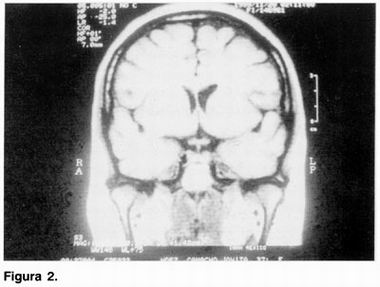

A su ingreso, se realiza BH, QS, ES, PFH, PF (tiroides, cortisol y prolactina), EEG y P-300 resultando dentro de límites normales. La IRM mostró asimetría en el sistema ventricular por mayor talla ventricular izquierda con datos sugestivos de atrofía subcortical de hemisferio izquierdo (figuras 1 y 2).

La paciente que presentamos cumple con los criterios clínicos y por imagen para catalogarla como síndrome de hemiparkinsonismo-hemiatrofía. La paciente presenta de inicio hemiparkinsonismo, derecho, se documenta hemiatrofia corporal derecha de al menos 2 cm como se describe previamente, 2 y las imágenes por RM muestran una franca asimetría ventricular por dilatación del ventrículo lateral izquierdo. Los datos de asimetría hemicorporal son objetivos y confiables debido a que en la paciente que es diestra se esperaría una asimetría hemicorporal izquierda, dato que no presento, y por el contrario, el hemicuerpo pr edominante en la paciente (derecho), es el que se encuentra más afectado. La respuesta favorable que encontro en nuestra paciente con farmacoterapia utilizada para el Parkinson idiopático va de acuerdo con lo anteriormente descrito en que el síndrome tiene una base patogénica similar al PI, pero con substratos genéticos diferentes debido a la respuesta al tratamiento y a la evolución más prolongada que se ha descrito.